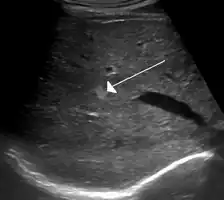

A cavernous liver hemangioma or hepatic hemangioma is a benign tumour of the liver composed of hepatic endothelial cells. It is the most common liver tumour, and is usually asymptomatic and diagnosed incidentally on radiological imaging. Liver hemangiomas are thought to be congenital in origin.[10] Several subtypes exist, including the giant hepatic hemangioma, which can cause significant complications.